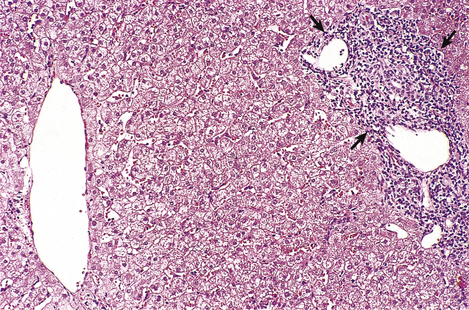

For many years the iron is deposited, as haemosiderin, in the hepatocytes without any clinical effects. Eventually, however, the iron deposition becomes more extensive, involving Kupffer cells, bile duct epithelium and portal tract connective tissue (Fig. 16.11). Hepatic fibrosis ensues, followed by cirrhosis. In advanced cases the haemosiderin is deposited in other tissues, notably in endocrine organs; the clinical syndrome of ‘bronze diabetes’ is due to concomitant iron-induced damage to the pancreatic islets (resulting in diabetes) and the effect of raised melanotrophin levels on the skin (resulting in bronze coloration). Cardiac failure and impotence may also result.

image

Fig. 16.11 Histology of haemochromatosis. The portal tract and the liver cells contain brown granules of haemosiderin. This has caused portal fibrosis and, if untreated, will eventually lead to cirrhosis.

If the condition is diagnosed in the pre-cirrhotic phase, the process may be arrested by depleting the body’s iron stores by regular venesection or by the administration of desferrioxamine, a chelating agent. The genetic aetiology of primary haemochromatosis means that it is important to screen first-degree relatives to identify those at risk from this potentially treatable liver disease.